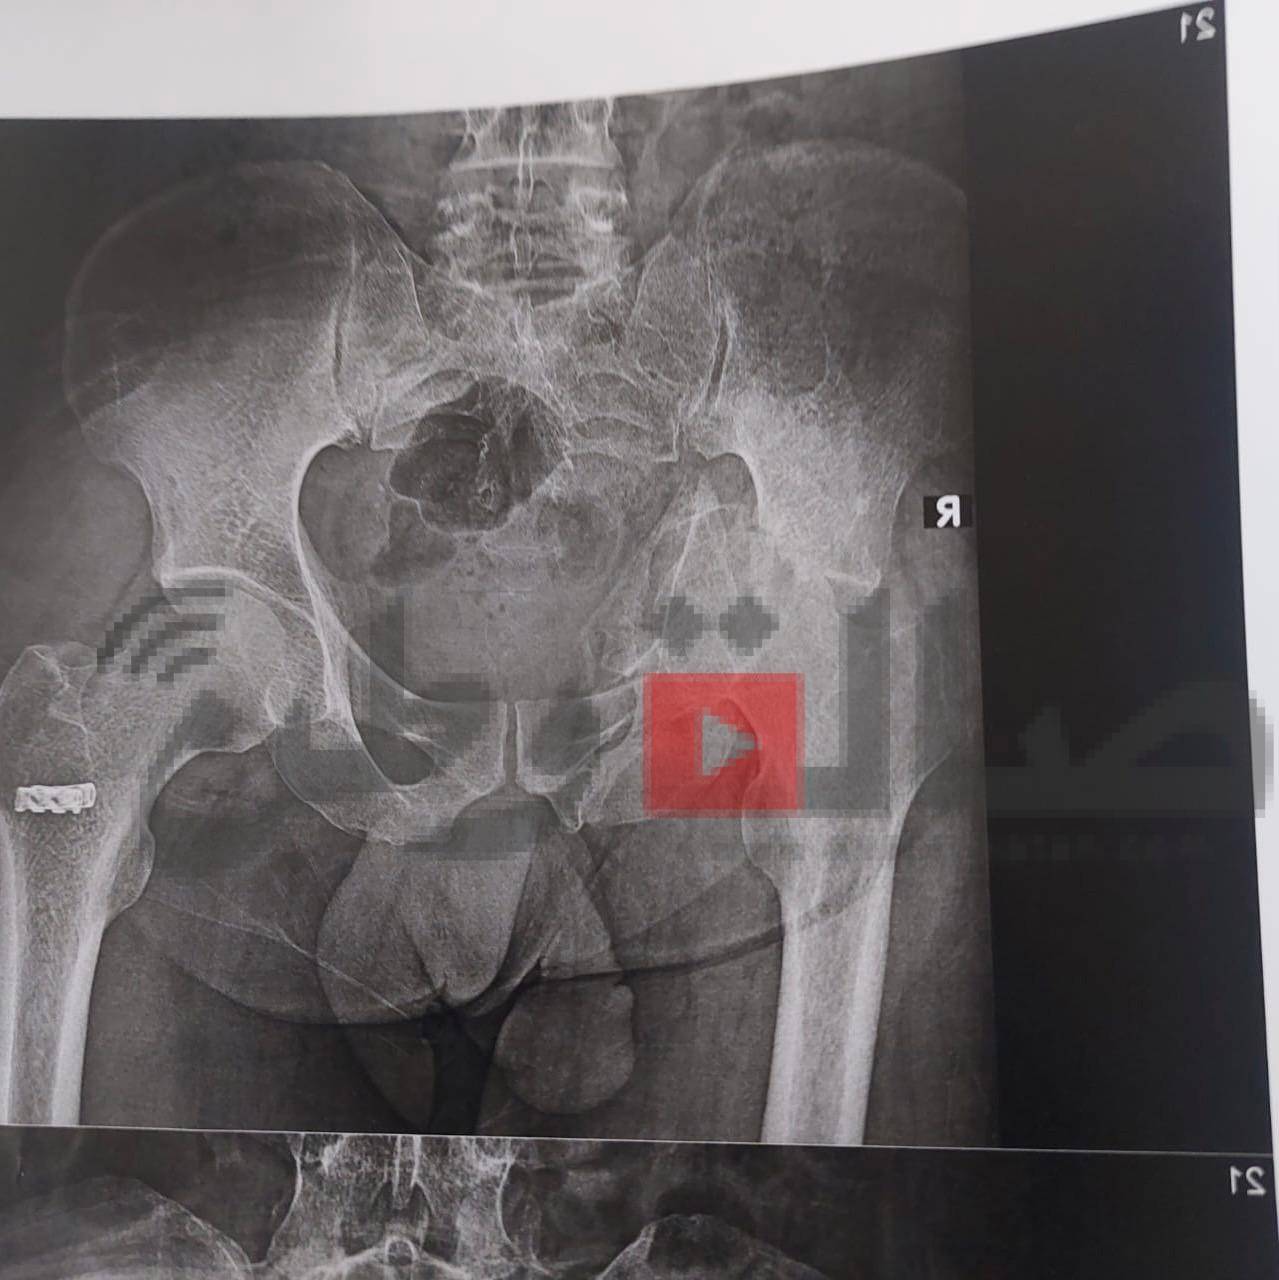

ومن جانبه قال الدكتور مجدي القاضي انه تم تقييم الحالة الصحية لأحد المرضي الأشقاء من أهالى غزة، ويبلغ من العمر 41 عاما ويعانى من خلع بمفصل الحوض منذ ٦ شهور، وعلى الفور تم إجراء العملية الجراحية للمريض وتركيب مفصل حوض كامل، مضيفاً أن ادارة المستشفي تولي اهتمام كبير ورعاية مستمرة لجميع مصابي غزة منذ ان وطأت اقدامهم داخل المستشفي الجامعي، وذلك تنفيذاً لتوجيهات الدكتور حسان النعماني رئيس الجامعة واهتمامه البالغ بمتابعته المستمرة لمستوي التحسن لحالتهم الصحية.

وقال الدكتور عبدالرحمن الشيخ انه تم استقبال المريض بقسم العظام وعمل الفحوصات والتحاليل المخبرية والاشاعات اللازمة وعلي الفور تم تشكيل الفريق الطبي المعالج الذي اجري العملية الجراحية ببراعة كبيرة، حيث بلغت تكلفة المفصل ٨٥ الف جنيه كتبرع من قسم العظام، موضحاً ان الفريق الطبي تكون من الدكتور ياسر عثمان استاذ جراحة العظام، الدكتور حسام حسنى والدكتور محمد شحاتة والدكتور عبدالرحمن بهاء مدرسين مساعدين بقسم العظام، الدكتور اسلام النحاس والدكتور مصطفى عبداللاه والدكتور يوسف راضى معيدين بقسم العظام، والدكتور على الشيخ والدكتور محمد جمال نواب سنيور بقسم العظام، بينما ضم فريق التخدير بقيادة الدكتور فوزي عباس كلاً من، الدكتور احمد عزمى مدرس مساعد تخدير، والدكتور عمرو عبد الصبور و الدكتورة ريهام رجب نواب سنيور بالقسم، وشكر خاص لفريق الهيئة التمريضية علي مابذلوه لإنجاز هذا العمل الانساني الكبير